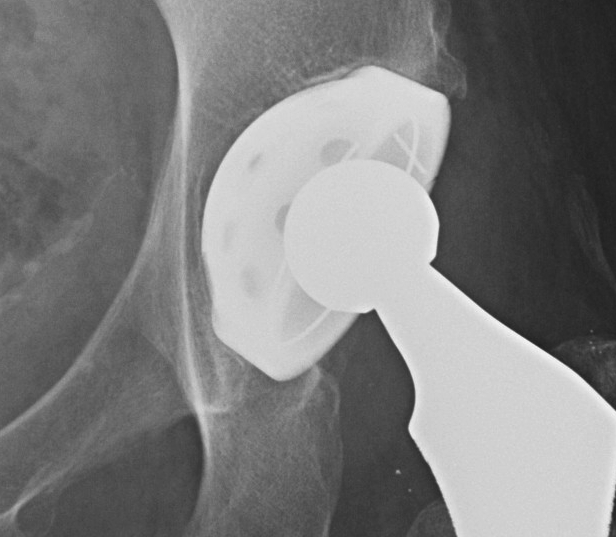

Uncemented Acetabular Component

Concepts

Radiographic signs of ingrowth fixation

Moore et al CORR 2006

- 3 or more 97% stable

- 2 or less, 83% unstable

Five signs

- absence of radiolucent lines

- presence of a superolateral buttress

- medial bone stress-shielding

- radial trabeculae

- inferomedial buttress

THR Uncemented Cup Superolateral Buttress 2

Engh Classification

I  Osse-ointegration

A  No RLL

B  One RLL zone 1 or 2

C  RLL zones 1 & 2

THR Uncemented Cup Stable RLL Zone 1Uncemented Cup No RLL

II Stable fibrous ingrowth

- <2mm zone 3

Uncemented Cup Stable Fibrous Ingrowth

III Unstable fibrous ingrowth

- >2mm RLL in zone 3